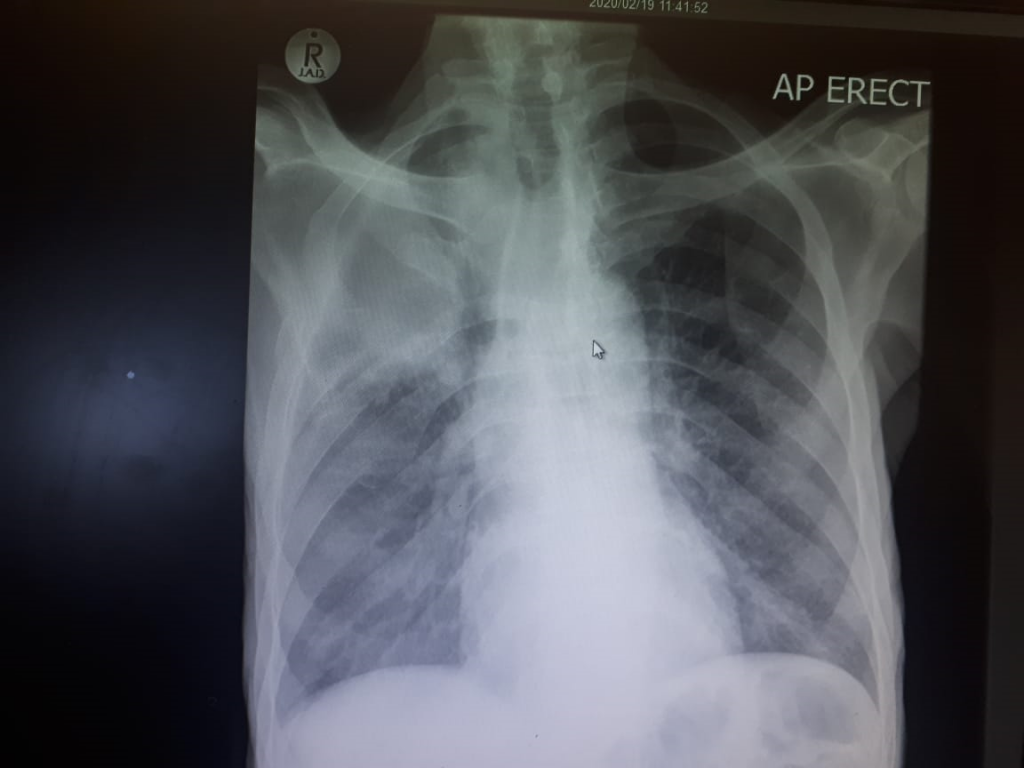

Other Investigations

The patient still had occasional vomiting, abdominal cramps and unexplained muscle pain – other electrolytes apart from calcium, magnesium and phosphate is also advised, as is osmolarity as fluid and electrolyte imbalance may be an effect, rather than a cause of the nausea, vomiting and muscle pain – the sodium and potassium was normal however.

- Primary hyperparathyroidism is on top of the differential diagnosis and is likely the cause of the raised total calcium.

- Other features of MEN-1 syndrome needs to be excluded.